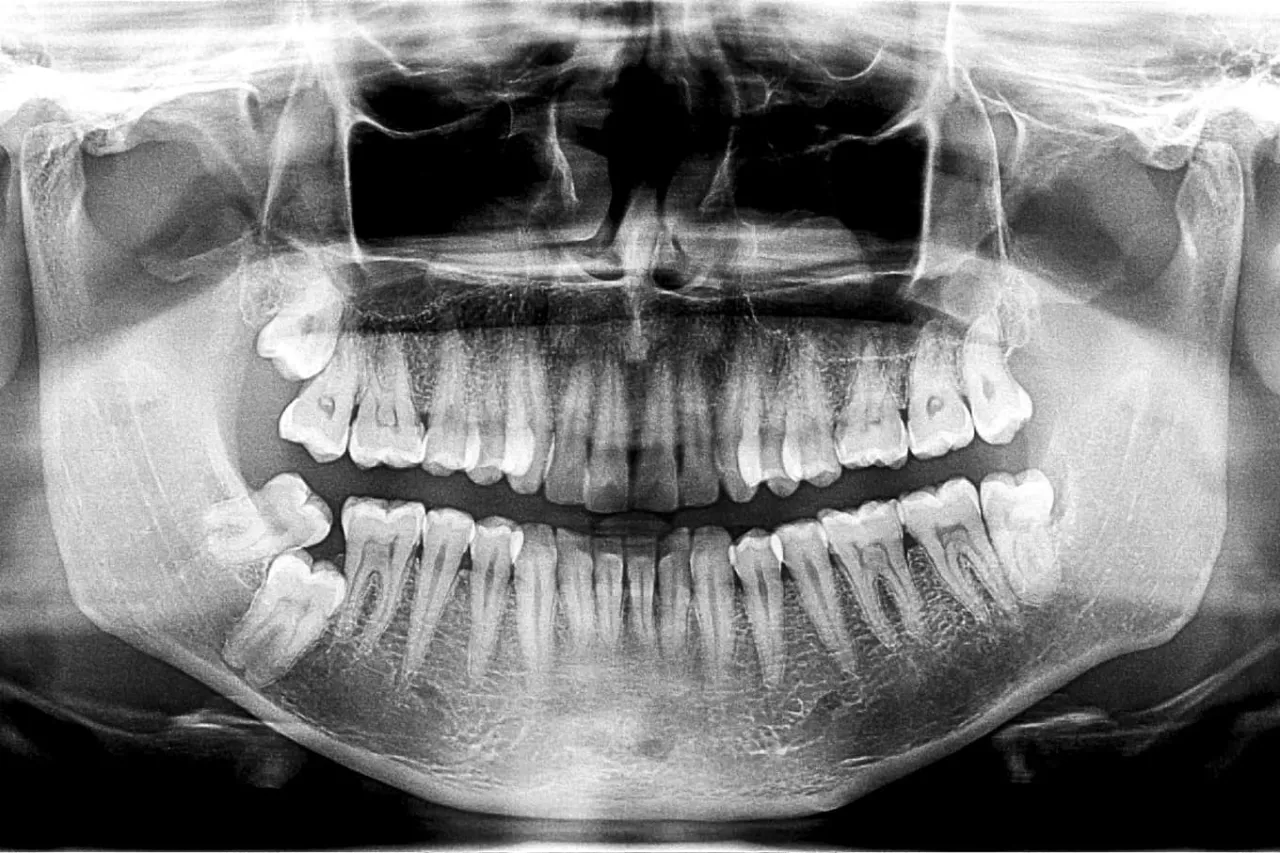

Kluczowy dowód: co widać na zdjęciu RTG zęba do leczenia kanałowego?

Jednak to zdjęcie rentgenowskie (RTG) jest kluczowym dowodem w diagnostyce. Najczęściej wykonuje się punktowe zdjęcie RTG, które pozwala mi zajrzeć w głąb zęba i ocenić stan tkanek niewidocznych gołym okiem. Na takim zdjęciu zęba kwalifikującego się do leczenia kanałowego mogę zaobserwować:

- Głęboki ubytek próchnicowy, który sięga miazgi lub jest bardzo blisko niej.

- Poszerzenie szpary ozębnej wokół wierzchołka korzenia, co świadczy o stanie zapalnym tkanek okołowierzchołkowych.

- Ciemne pole (tzw. rozrzedzenie struktury kostnej) wokół wierzchołka korzenia, które jest wyraźnym sygnałem toczącego się procesu zapalnego lub torbieli.

Dzięki RTG mogę dokładnie zaplanować leczenie i ocenić rokowania.

Nowoczesna diagnostyka: kiedy potrzebna jest tomografia CBCT?

W bardziej skomplikowanych przypadkach, zwłaszcza gdy anatomia zęba jest nietypowa lub wcześniejsze leczenie kanałowe nie przyniosło rezultatów, mogę zlecić wykonanie pantomogramu (zdjęcia panoramicznego całej szczęki) lub, co coraz częstsze, tomografii komputerowej wiązki stożkowej (CBCT). Ta trójwymiarowa technika obrazowania dostarcza niezwykle precyzyjnych informacji o budowie kanałów, zmianach okołowierzchołkowych i ewentualnych pęknięciach korzenia, co jest nieocenione w trudnych przypadkach.